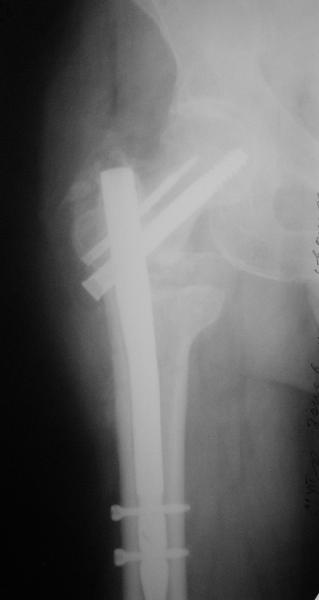

Как предлагали уважаемые коллеги, сегодня наложили спице-стержневой дистрактор таз-бедро, перед этим попробовали закрытую остеоклазию под в/в анестезией, движение в т/б суставе ( или в ложном суставе! ) восстановлен.

Р-снимки сразу п/о, следующий после дистракции, аксиальная - прощу извинения за плохое качество снимков.

Мне кажется надо еще продолжать постепенную дистракцию. И еще которая наверху шейки по моему это осколок от шейки, и она фиксирована оссификатом надвертлужной обл. Поэтому при повторной операции видимо придется открыто мобилизовать т/б сустав.

С уважением Абдурашид.